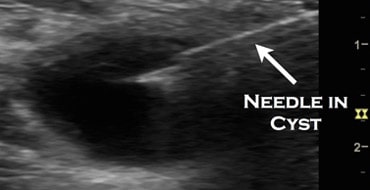

USG Guided Cyst Aspiration

An ultrasound-guided cyst aspiration is a minimally invasive procedure in which ultrasound is used to locate a cyst and guide a thin needle into the cyst to remove the fluid. It is used for the simple (non-cancerous) cyst, filled with clear fluid. It is usually done under IV sedation / G.A. via vaginal route.